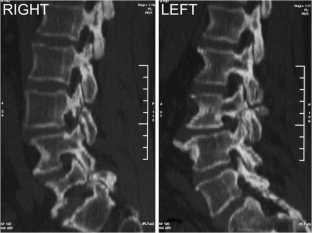

Atypical, unusual, and misleading imaging presentations of spondylolysis

Although lumbar spondylolysis is a widely known and easily recognizable condition in its typical presentation, there are some less well-known forms that may occasionally be challenging and/or demand special attention on imaging. Examples include: acute and/or incomplete lesions; unilateral defects; lesions at unusual levels (cervical, upper lumbar, and multi-level spondylolyses); iatrogenic lesions; non-isthmic spondylolysis; and spondylolysis related to underlying diseases. In addition to their atypical, uncommon or confusing imaging presentations, these forms of spondylolysis are far rarer than the classic type and have been described, to a great extent, in the surgical literature, thus reducing the awareness of radiologists about them and raising the potential for misdiagnosis and inadequate treatment. In this review the authors address these special manifestations of spondylolysis, stressing the more important features to be considered in the differential diagnosis and the impact of a precise diagnosis of spondylolysis on the patient’s care.